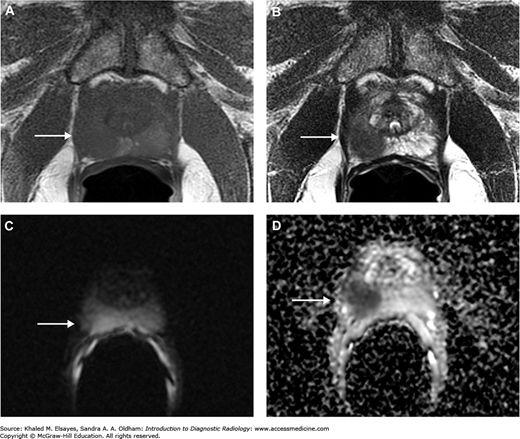

MRI with endorectal coil of a patient with prostate cancer. (A) Axial T1WI. (B) Axial T2WI. (C) DWI. (D) ADC map reveals a well-defined focal lesion exhibiting an isointense signal on T1WI and hypointense on T2WI, with restricted diffusion (arrow).